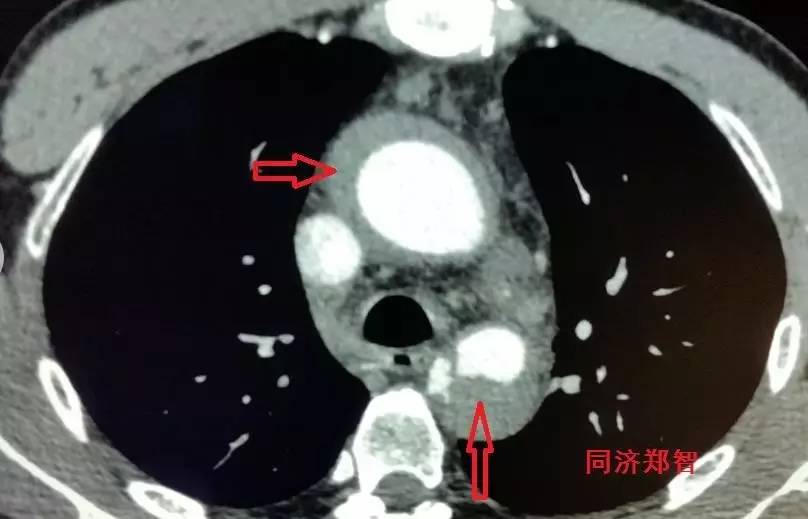

胸降主动脉穿透性溃疡合并壁间血肿(图6),心底层面红箭头所示。

图6